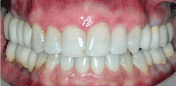

The final restorations were inserted 8 months postsurgically (Figures 8-11). An occlusal splint was fabricated and delivered after the completion of restorative phase (Figure 12). All the final treatments after the initial 5-year period were performed by the last author and his team.

Figure 8. Post-operative clinical view in maximum intercuspal position.